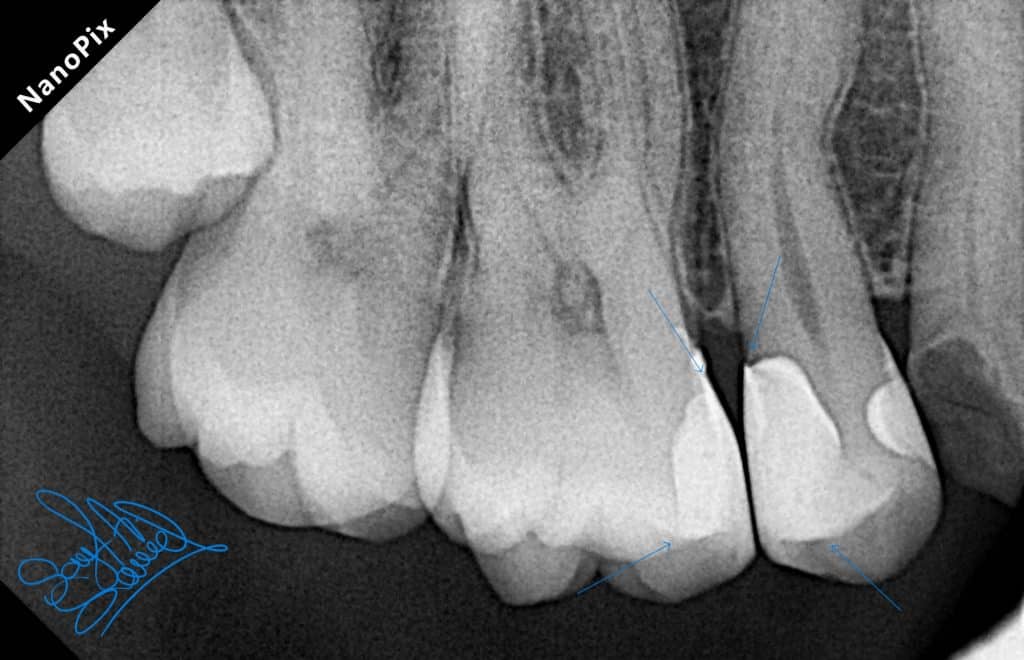

Initial situation

Caries excavation and cavity design